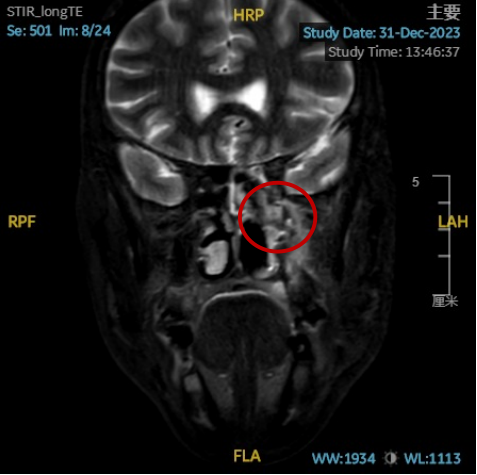

丁小军团队在鼻内镜术中发现:肿物向前下方附着于前颅底,翼管神经、上颌神经和腭大神经已贯穿入肿瘤内部,情况非常复杂和艰难!历时三个半小时,终于从颅底骨质**肿物和肿物所侵犯的神经全部分离和切除。术后磁共振检查显示:肿物完全切除,翼内肌、翼外肌安全保留。